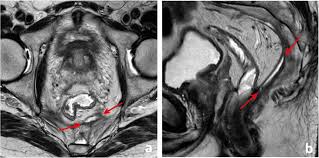

When Colon Cancer Spreads To Your Bones Symptoms Diagnosis Treatment Bone Care from img.webmd.com Lymphoma is a type of cancer that affects the lymphatic system. Lymphosarcoma, which affects the gastrointestinal system's lymph nodes, and adenocarcinoma, which leads to the growth of one or more tumours in the body's apocrine glands, which lie parallel to each other on the rectum. There are two types of colon cancers that can affect dogs: Rectal polyps in dogs can be small or large in size. This type of cancer creates a secretion that increases calcium in the blood and can damage the kidneys. So, whatever you take away from this article, do run it through your vet. Of course, it all depends on the dog's breed, age and when cancer is detected. Prostate cancer in dogs is a rare but deadly form of cancer that can easily metastasize and spread to other organs and areas of the body, including the lungs, bones, and lymph nodes.

As our dogs get older, they are at a greater risk for many diseases, including cancer. Rectal tumors are more common in dogs. Fifty percent of dogs over the age of 10 develop cancer at some point. Treating stage 0 rectal cancer They can be harmless (benign) tumors or aggressive (malignant) tumors that spread to other parts of the body. Breeds known to be at risk for this form of cancer include the spaniel breeds; Different types of colon cancer in dogs there are two main forms of colon cancer that can affect dogs; Usually seen as a rectal growth (mass) on the animal, it also is common to find the disease in the lymph nodes. As we find in humans, the cause of cancer is not always easily discovered. Dogs with hypercalcemia, or elevated blood calcium levels, may also be more likely to develop it. Prostate cancer in dogs is a rare but deadly form of cancer that can easily metastasize and spread to other organs and areas of the body, including the lungs, bones, and lymph nodes. The growth of malignant tumors of this type can occur in many parts of the body, including the gastrointestinal tract of the dog. An adenocarcinoma will cause a tumor growth within the apocrine glands in a dog, which are located near the rectum.